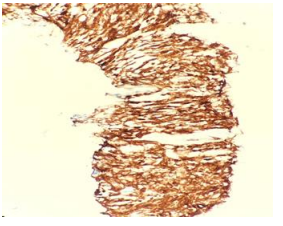

• CEMRI Brain (OCT 2024): Large, solid-cystic hemorrhagic metastatic masses were noted in the bilateral temporo-occipital regions. These lesions caused significant perilesional edema, midline shift, and extensive bone involvement. (Fig.1)

FIG 1: CE MRI BRAIN SEP 24

Figure 1